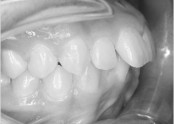

• 치아교정 돌출입 교정

• 치아교정 덧니 교정